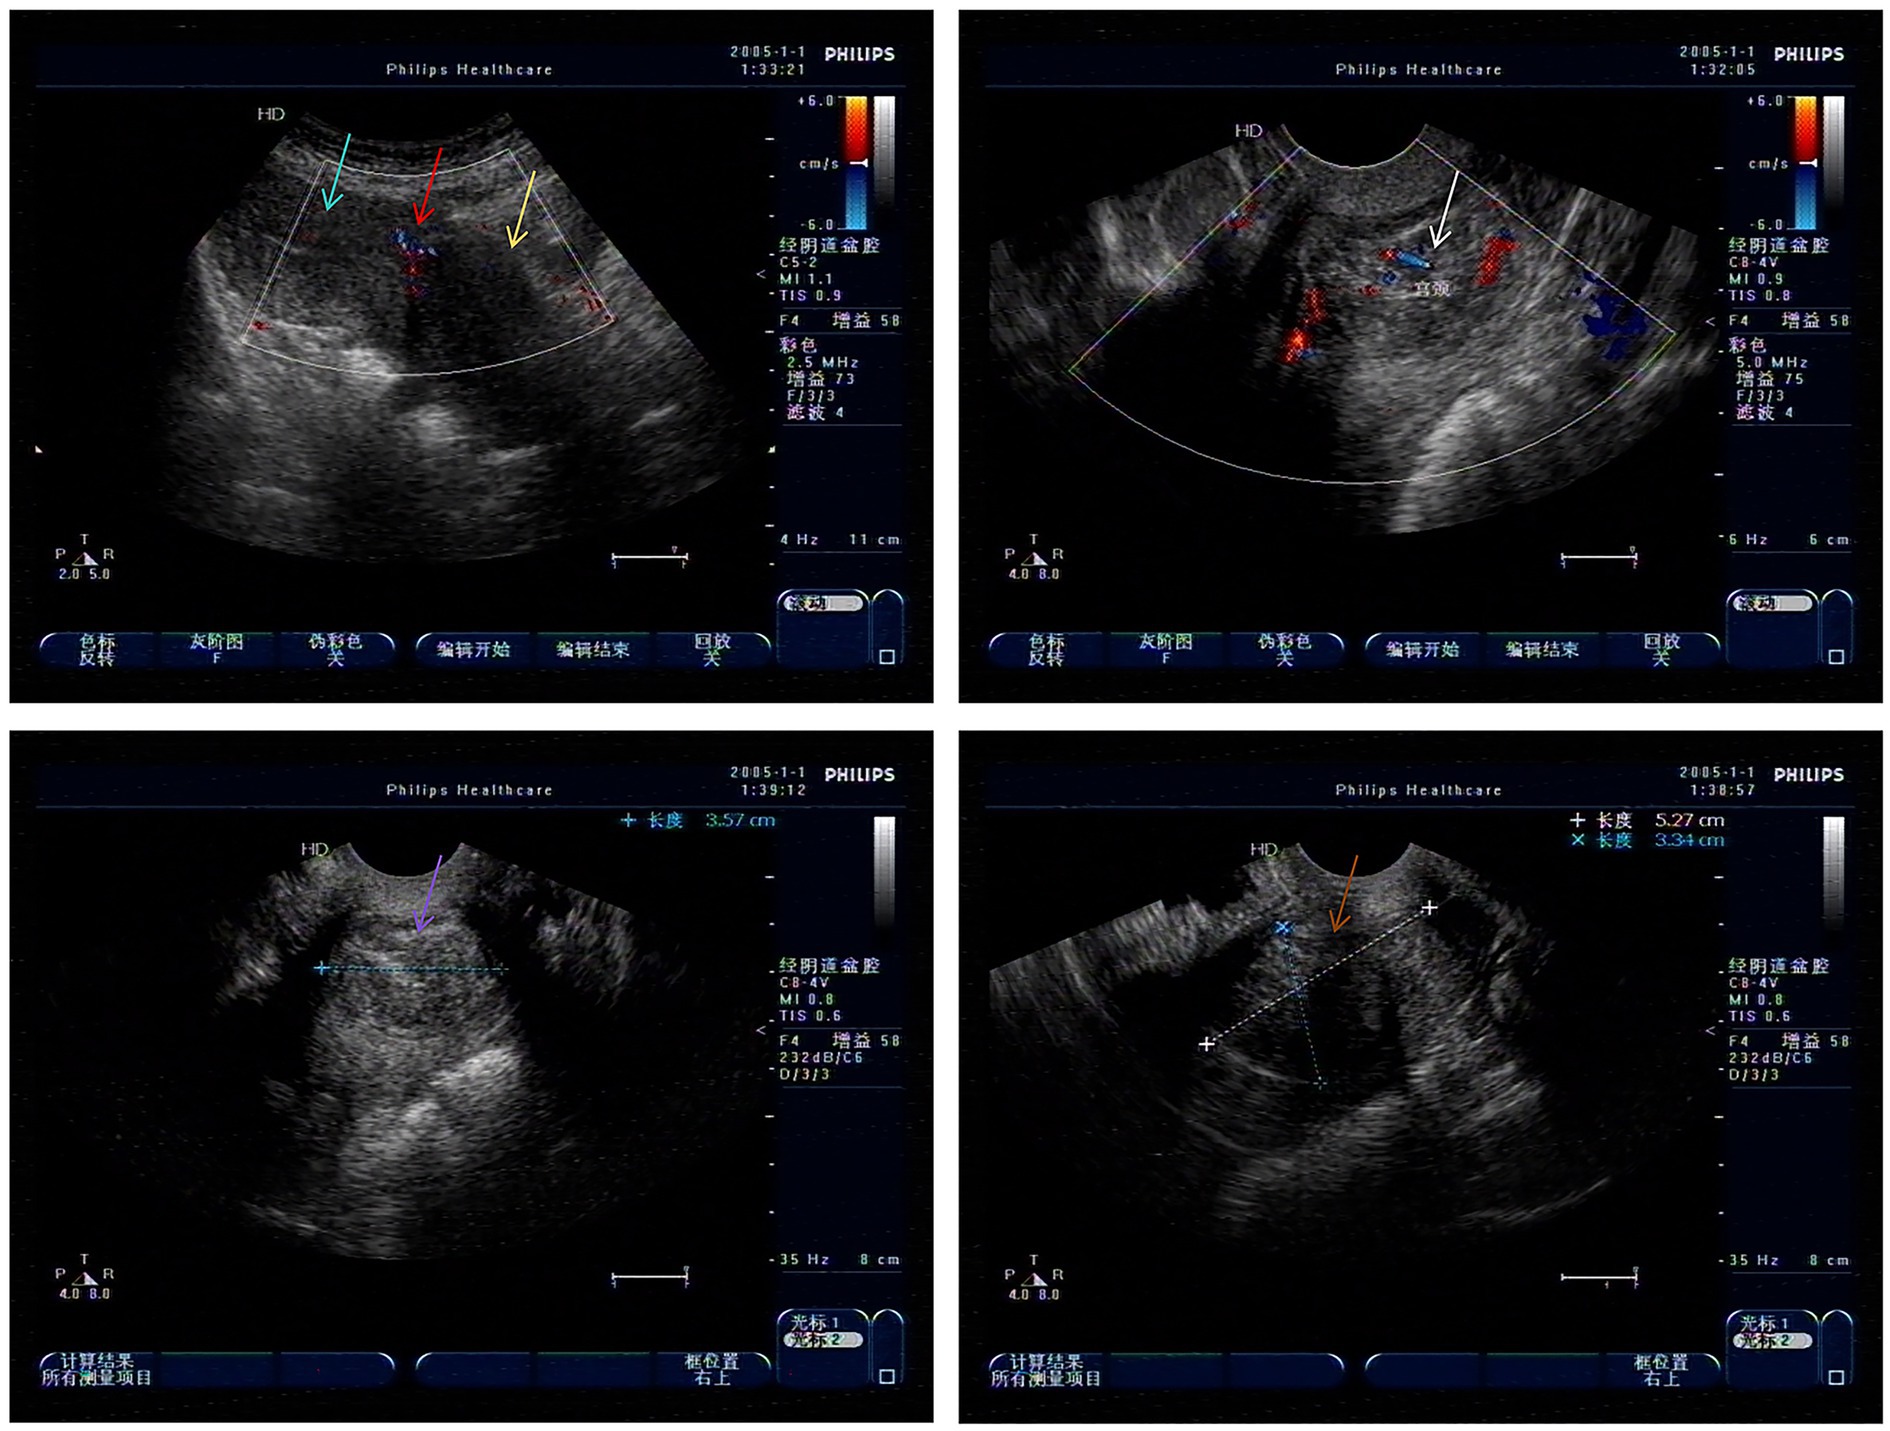

A 49-year-old G1P1 (1999 cesarean delivery) presented with 2 years of menorrhagia (10–15 days/cycle) and worsening fatigue. Ultrasound showed a 5.3 cm × 3.5 cm × 3.3 cm heterogeneous cervical mass (Figure 2). The physical examination showed an enlarged uterus, approximately the size of 11 cm × 8 cm × 7 cm. Hematologic workup showed the hemoglobin (HGB) level of 65 g/L. Based on these examination results, a clinical diagnosis of “uterine fibroids, secondary anemia” was conducted. Preoperative preparation was improved by administering 600 mL of red blood cell suspension to correct anemia. After the HGB reached 94 g/L, misoprostol was administered to soften the cervix for 3 days.

Figure 2. Low echo of cervical canal in gynecological ultrasound examination (Green arrow: uterine body; Red arrow: uterine scar; Yellow arrow: cervical area; White arrow: Cervical hypoechogenicity and blood flow; Purple and brown arrow: Cervical hypoechogenicity).